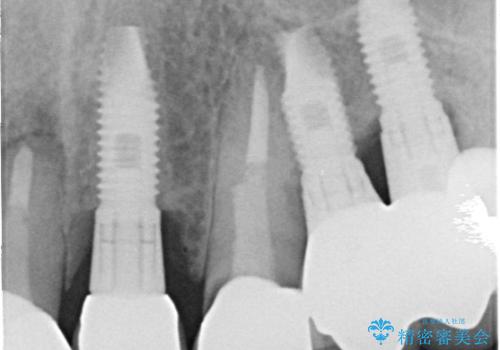

- 「被せ物が揺れている」を主訴に来院された患者様です。診査診断を行い被せ物が外れているのではなく、コアという土台ごと外れていたので、土台ごとやり変えた後オールセラミッククラウンで治療を行いました。

ファイバーコアという土台を建てるときに唾液が入ると接着に良くないのでラバーダムシートを使用しています。加えてマイクロスコープを使用しながら行う事で外れにくい土台を作ることが出来ます。その後、形成を行いシリコンで型取りしたのち、オールセラミッククラウンで修復しました。